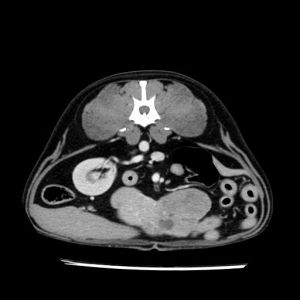

La lesione focale epatica , la ceus,la Tac e il chirurgo .